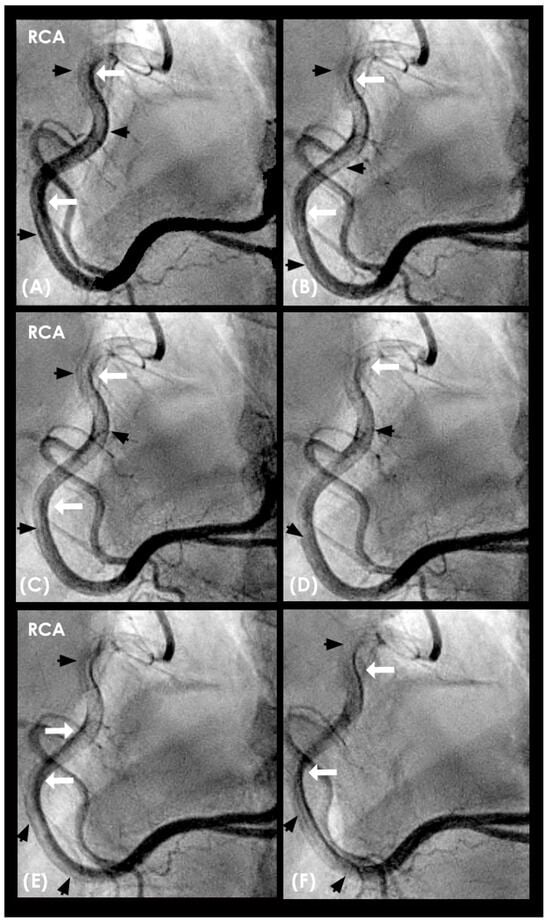

Dynamic Coronary Angiography. In a shift in strategy, our research adopted a novel approach by conceptualizing the cardiovascular system as an interconnected network of pipes and pumps, paving the way for the development of an innovative angiographic technique capable of capturing real-time coronary flow dynamics [2]. Drawing experiences from fluid mechanic engineering, where flow disturbances compromised the integrity of pipe surfaces, we hypothesized that analogous forces may damage the arterial intima. Accordingly, our analysis emphasized the characterization of blood flow—whether laminar, recirculating, disorganized—and its correlation with the initiation, progression, or regression of coronary lesion as seen in Figure 3 [3].

This approach defines baseline flow as antegrade and laminar, with deviations considered abnormal. Retrograde flow colliding with antegrade flow is a primary mechanism of vascular injury. A thick lateral contrast layer may indicate prolonged, subtle intimal damage, potentially leading to gradual lesion formation. Laminar flow supports long-term coronary patency.

Figure 3. (AD) Laminar flow. These four coronary images are of consecutive sequence. (A) This is the angiogram of the right coronary artery (RCA), which is filled with contrast in black. (B) The blood (in white) is seen well organized with sharp border and a pointed tip, typical for laminar flow, moving in (yellow arrow). (C,D) The blood is seen following the apex of the curves (yellow arrow). This is the laminar flow following the curves in a helical fashion.